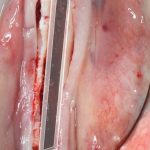

Обычно, через день после операции рана выглядит вот таким образом:

А сам пациент — как-то так:

Отёк, болезненные ощущения, затрудненное открывание рта — вполне себе обычная симптоматика после подобных операций. Впрочем, как и после остеопластик другими методами.